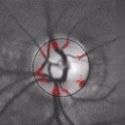

Here are retina images from twins / Ci-dessous deux rétines de jumeaux:

A kind of (circular) barcode is extracted from the pattern of blood vessels, which is stored for further comparison with a new retina image.

First the intensity profile is extracted, then a circular scan is performed to locate blood vessels.